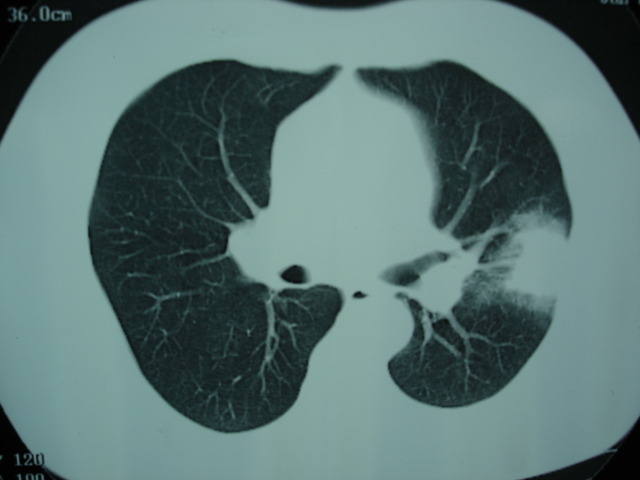

2009.6.4 2009.6.7 2009.8.21

第一次ct2009.6.4